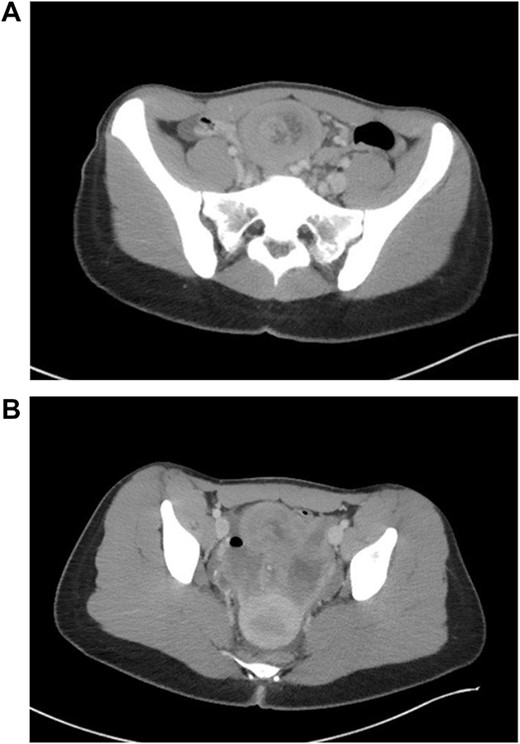

Patient is a 21-year-old female who presented with severe, sudden onset abdominal pain with associated poor oral intake, nausea and vomiting. Patient’s only past medical history was remarkable for normocytic anemia found on lab work. Patient did not report any significant family history. As a part of the patient’s initial work-up a computed tomography (CT) of the abdomen and pelvis with IV contrast was obtained with evidence of intussusception of a long segment of small bowel in the lower midline abdomen extending into the pelvis, measuring ~15 cm in length (Fig. 1); the patient’s CT was not remarkable for pneumatosis or obstruction.